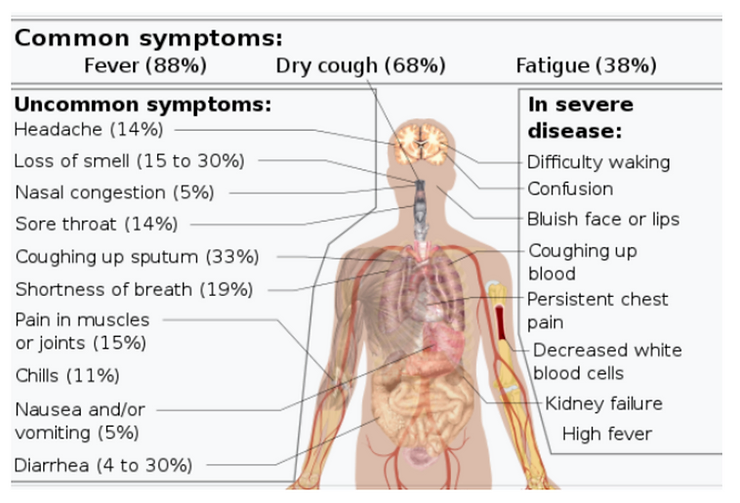

What are the Symptoms of Pathological Blood Coagulation & SARS-CoV-2 & 12?[13][14][15]

1) Cold hands and cold feet

2) Light headedness

3) Muddled thinking

4) Neuropathy of the extremities

5) Tingling in the toes

6) Dry cough

7) Frequent cough

8) Wheezing

9) Choking sensation

10) Waking up out of breath

11) Bluish discoloration of the skin

12) Shortness of breath while resting

13) Severe shortness of breath after physical activity

14) Fever

15) Shortness of breath

16) Low energy

17) Fatigue

18) Blurred vision

19) Hearing loss

20) Loss of taste

21) Night sweats

22) Aches or pains in the muscles

23) Joint Pain

24) Dizziness

25) Itching

26) Skin blemishes

27) Nausea

28) Bowel irritation and elimination problems

29) Hypoxia

30) Hypoxemic

31) Hypercapnia